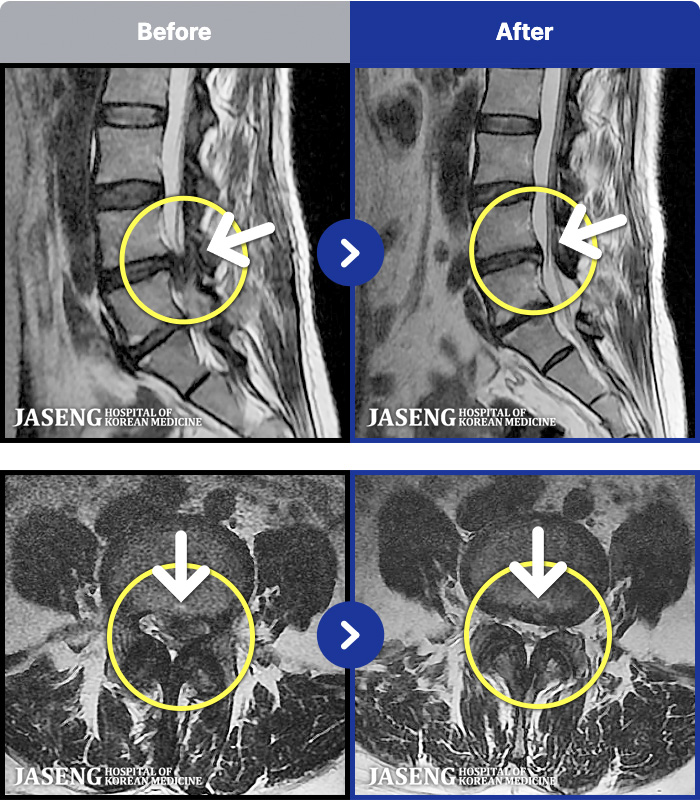

1,291 MRI ũ ʸ Ȯϼ.

[] 03.04.01~09.11.01